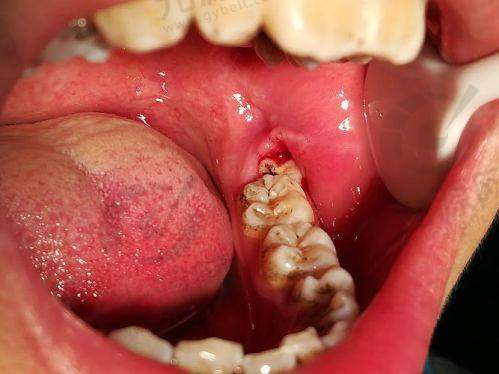

智齿拔牙后7天窟窿状态

智齿拔牙后的第7天是反映愈合成效的重要时间点。这时,拔牙后的窟窿开始出现了明显的变化,生长出的肉芽组织也开始形成,填补了牙槽窝。大部分患者在此时会感觉到疼痛减缓,肿胀也有所缓解。

根据临床数据,80%的患者在7天内可以看到伤口表面有了一定的愈合,牙槽窝的深度明显缩小。在这一阶段,保持口腔卫生至关重要,避免刺激物入侵伤口,能够有效降低感染风险。

此时一些患者可能会发现食物残渣更容易滞留在牙洞中,建议进行一些简单的漱口清洁处理,帮助清理伤口周围的残余物。